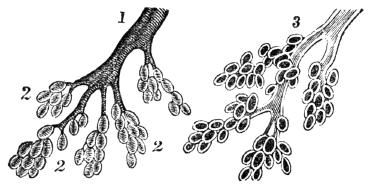

| 23. | Anatomy of the Respiratory Organs, | 209 |

| 24. | Physiology of the Respiratory Organs, | 217 |

| 25. | Hygiene of the Respiratory Organs, | 228 |